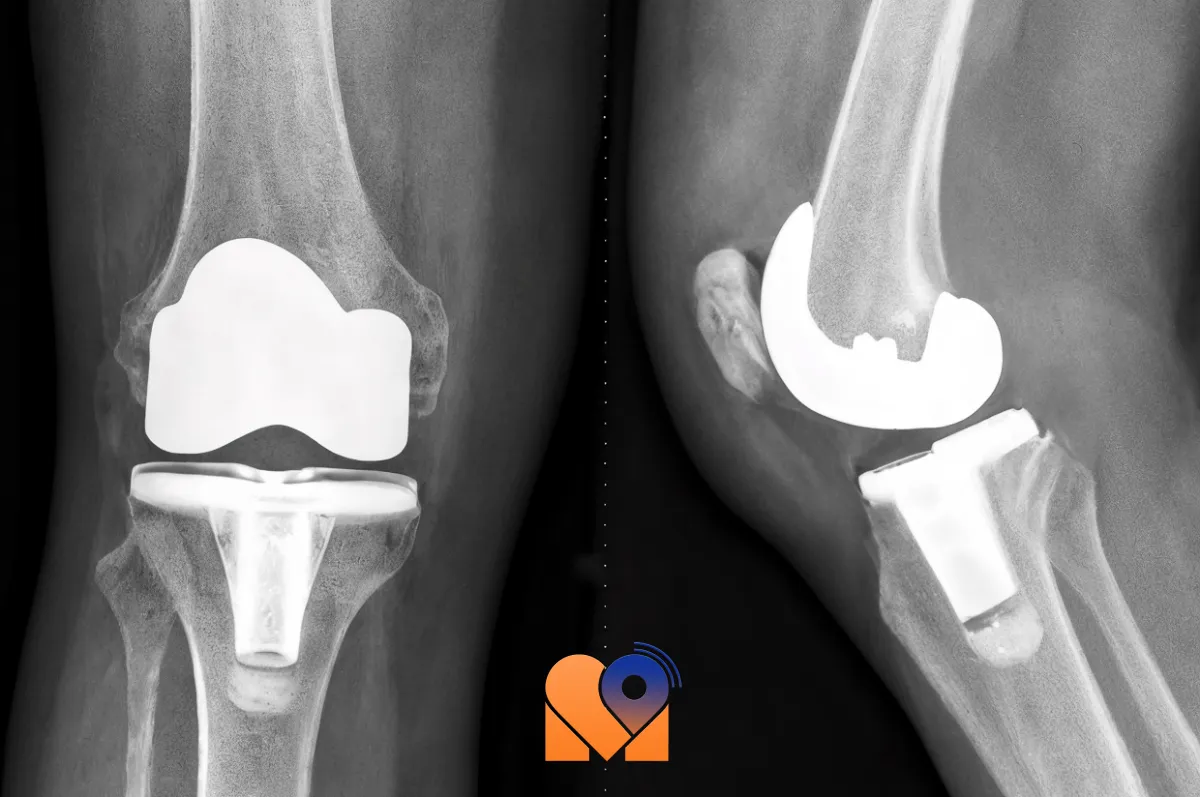

تعویض مفصل زانو یا جراحی آرتروپلاستی زانو یکی از پیشرفته ترین روشهای جراحی در حوزهی ارتوپدی است که با هدف بازگرداندن عملکرد طبیعی زانو و کاهش دردهای مزمن انجام میشود. در این عمل، سطوح آسیب دیدهی مفصل زانو که بر اثر آرتروز، تخریب غضروف، یا صدمات شدید دچار فرسایش شدهاند، با اجزای مصنوعی (پروتزهای مخصوص مفصل زانو) جایگزین میشوند. این پروتزها از مواد زیست سازگار مانند فلز، پلیاتیلن یا سرامیک ساخته میشوند تا با بدن سازگاری کامل داشته باشند و حرکت طبیعی زانو را شبیه سازی کنند.